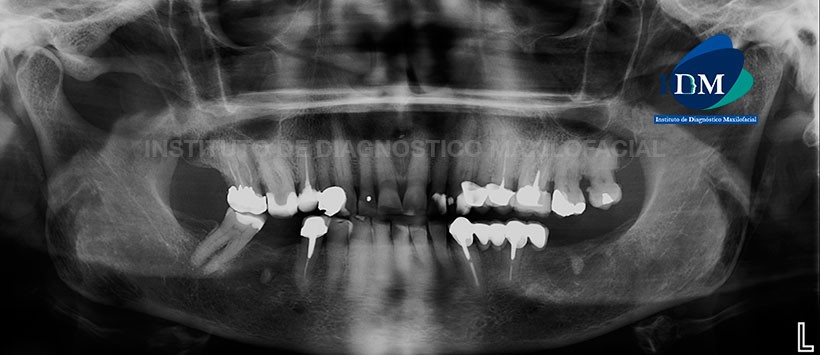

Paciente de sexo femenino de 87 años de edad acude al Instituto de Diagnostico maxilofacial para evaluación de las molares del cuadrante dos.

A la evaluación de la radiografía panorámica se pudo apreciar mineralización de ambos procesos estilohioideos, neumatización alveolar y engrosamiento de la mucosa basal de ambos senos maxilares, apiñamiento y faceta de desgaste coronario del sector dentario anterior (atrición), leve reabsorción ósea alveolar bimaxilar, ausencias de piezas dentarias así como múltiples restauración y piezas con material de obturación de conductos. Sin embargo, en la pieza 26 se puede evidenciar material de obturación en las raíces palatina y distovestibular mientras que en la raíz mesial se puede evidenciar la ausencia de material de obturación juntos con un proceso osteolítico apical. Adicionalmente se aprecia un espigo metálico interradicular con corona protésica la cual tiene una ligera falta de sellado cervicodistal.

En la pieza 27 y 28 se evidencio presencia de un aumento de la densidad perirradicular, placa dental mineralizada en zona cervical y material de restauración coronario. (Figura 1)